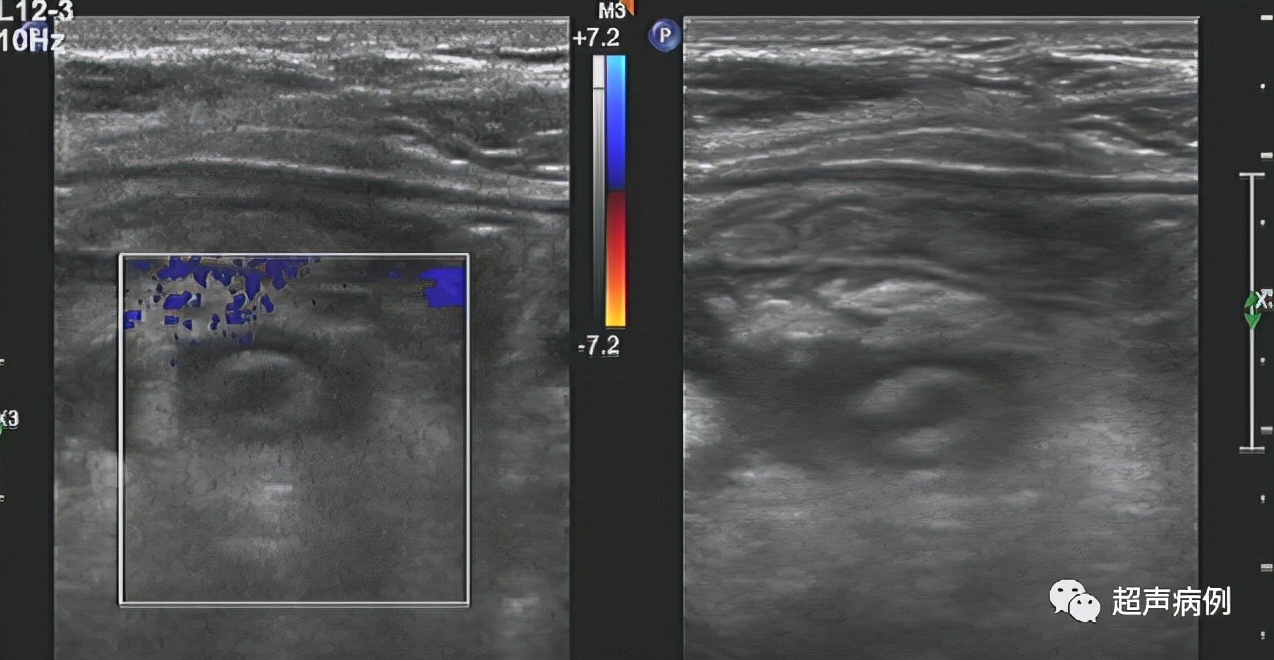

病例4

男,43岁。转移性右下腹痛2天

超声检查:

右下腹阑尾解剖区查见一范围约3.7x1.2cm管状弱回声,其内可见团状强回声,周边组织回声增强。CDFI:未见明显血流信号。

病理诊断:急性坏疽性阑尾炎及其周围炎。